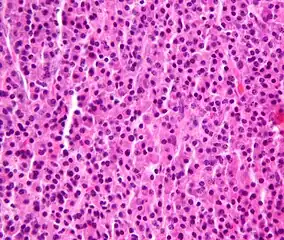

Micrograph of a plasmacytoma. -

Micrograph of a plasmacytoma. H&E stain.